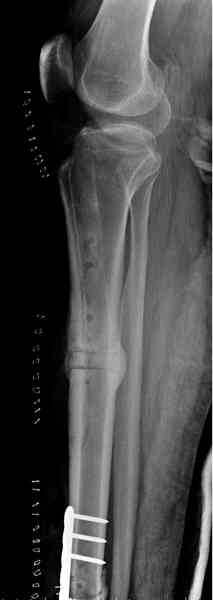

"При его рассмотрении с рентгенологом и морфологом сошлись, что это не фиброзная дисплазия, что было первым предположением по рентгенограммам. В полости было и мягкотканое образование. Окончательно заключение дадут через несколько дней"

По локализации и по характреру опухоли мало напоминает остеобластому, может, представленные биопсийные материалы адамантиномы помогут вашим морфологам дифференцировать опухоль (Basiloid cells, pseudoglandular pattern and peripheral palisading)

К нашему онкологу-ортопеду обратился больной с жалобами на боли в голени, из рассказа - год назад была сделана биопсия большеберцовой кости, но название заболевания "не запомнил”.

В литературе "A Classic Adamantinoma Arising from

Osteofibrous Displasialike Adamantinoma in the Lower Leg: A case report and Review of the Literature похожие снимки.

Снимки представлены.